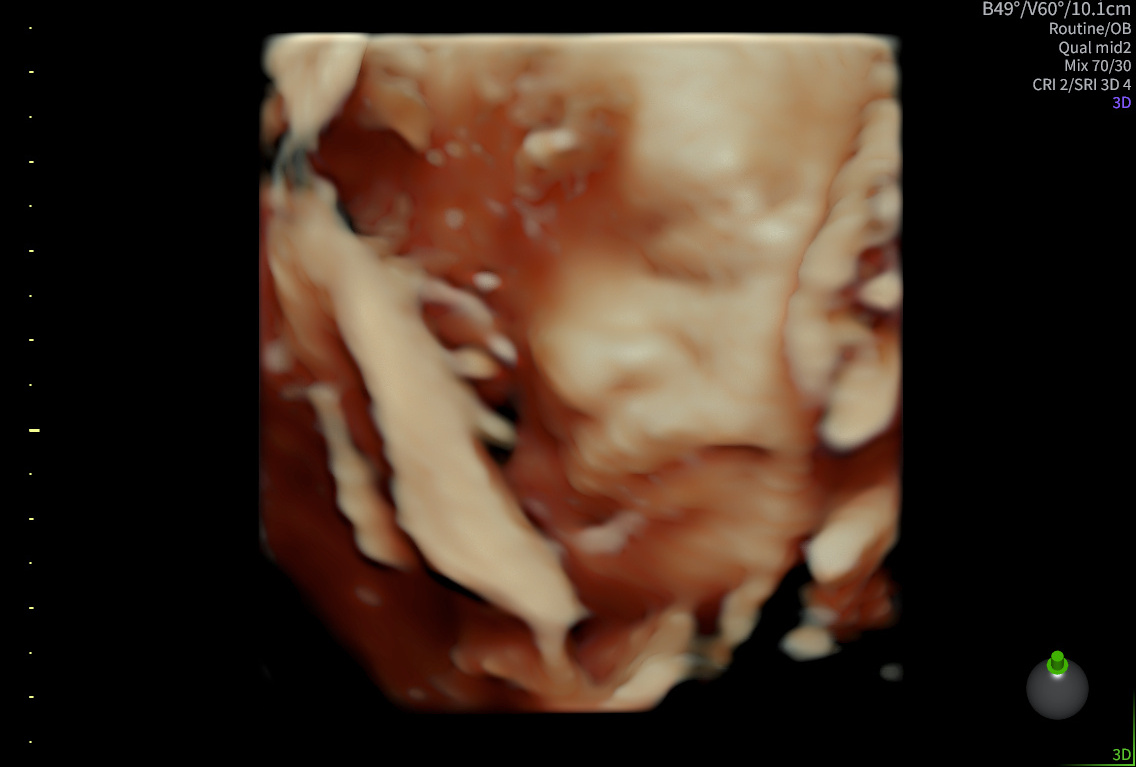

3D/4D-scanning

Realistiske billeder uge 25–30

1.095 kr. / 1.045 kr. returkunde